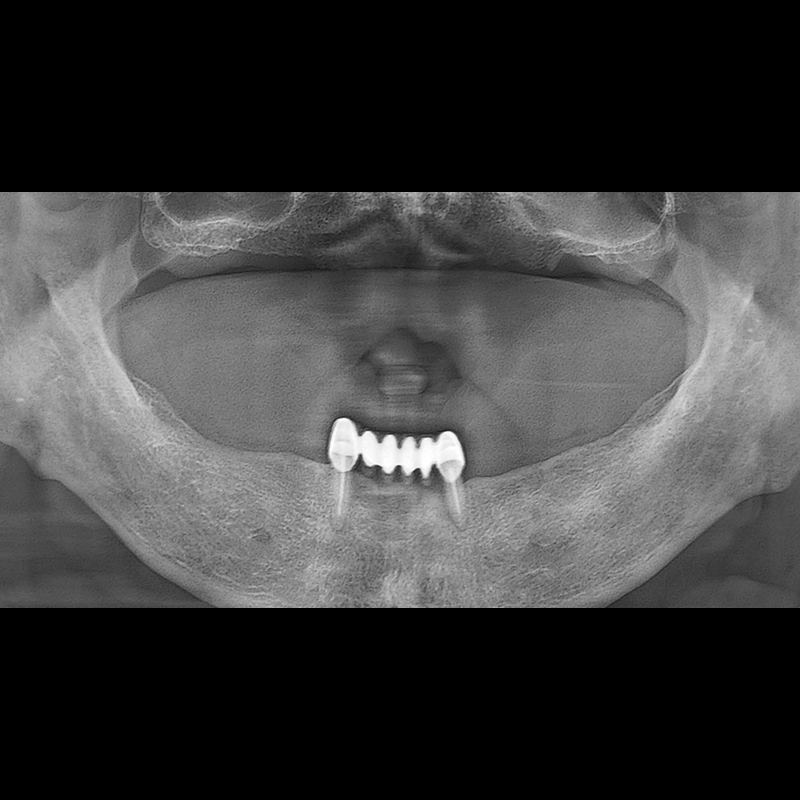

BEFORE AFTER

インプラント手術事例 2025.05.30

欠損した歯の部分と、生かしにくい歯の位置にインプラントを植立しました。